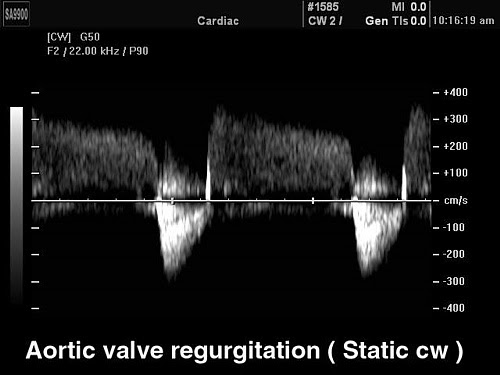

CW постоянно-волновой допплер

В эхокардиографии с помощью постоянно-волнового допплера производят расчеты давления в полостях сердца и магистральных сосудах в ту или иную фазу сердечного цикла, рассчитать степень значимости стеноза